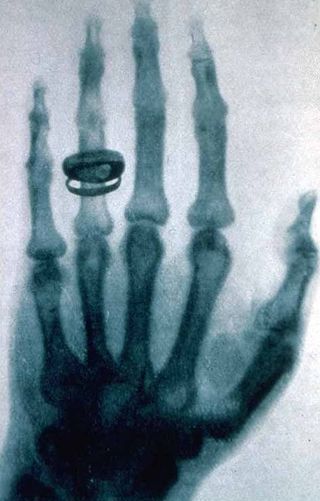

X-ray of a hand. X-rays are a common medical test.  | |